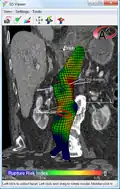

An aneurysm ruptures if the mechanical stress (tension per area) exceeds the local wall strength; consequently, peak wall stress (PWS),[32] mean wall stress (MWS),[33] and peak wall rupture risk (PWRR)[34] are more reliable parameters than diameter to assess AAA rupture risk. Medical software allows computing these rupture risk indices from standard clinical CT data and provides a patient-specific AAA rupture risk diagnosis.[35][36][37] This type of biomechanical approach has been shown to accurately predict the location of AAA rupture.[36][37][38]